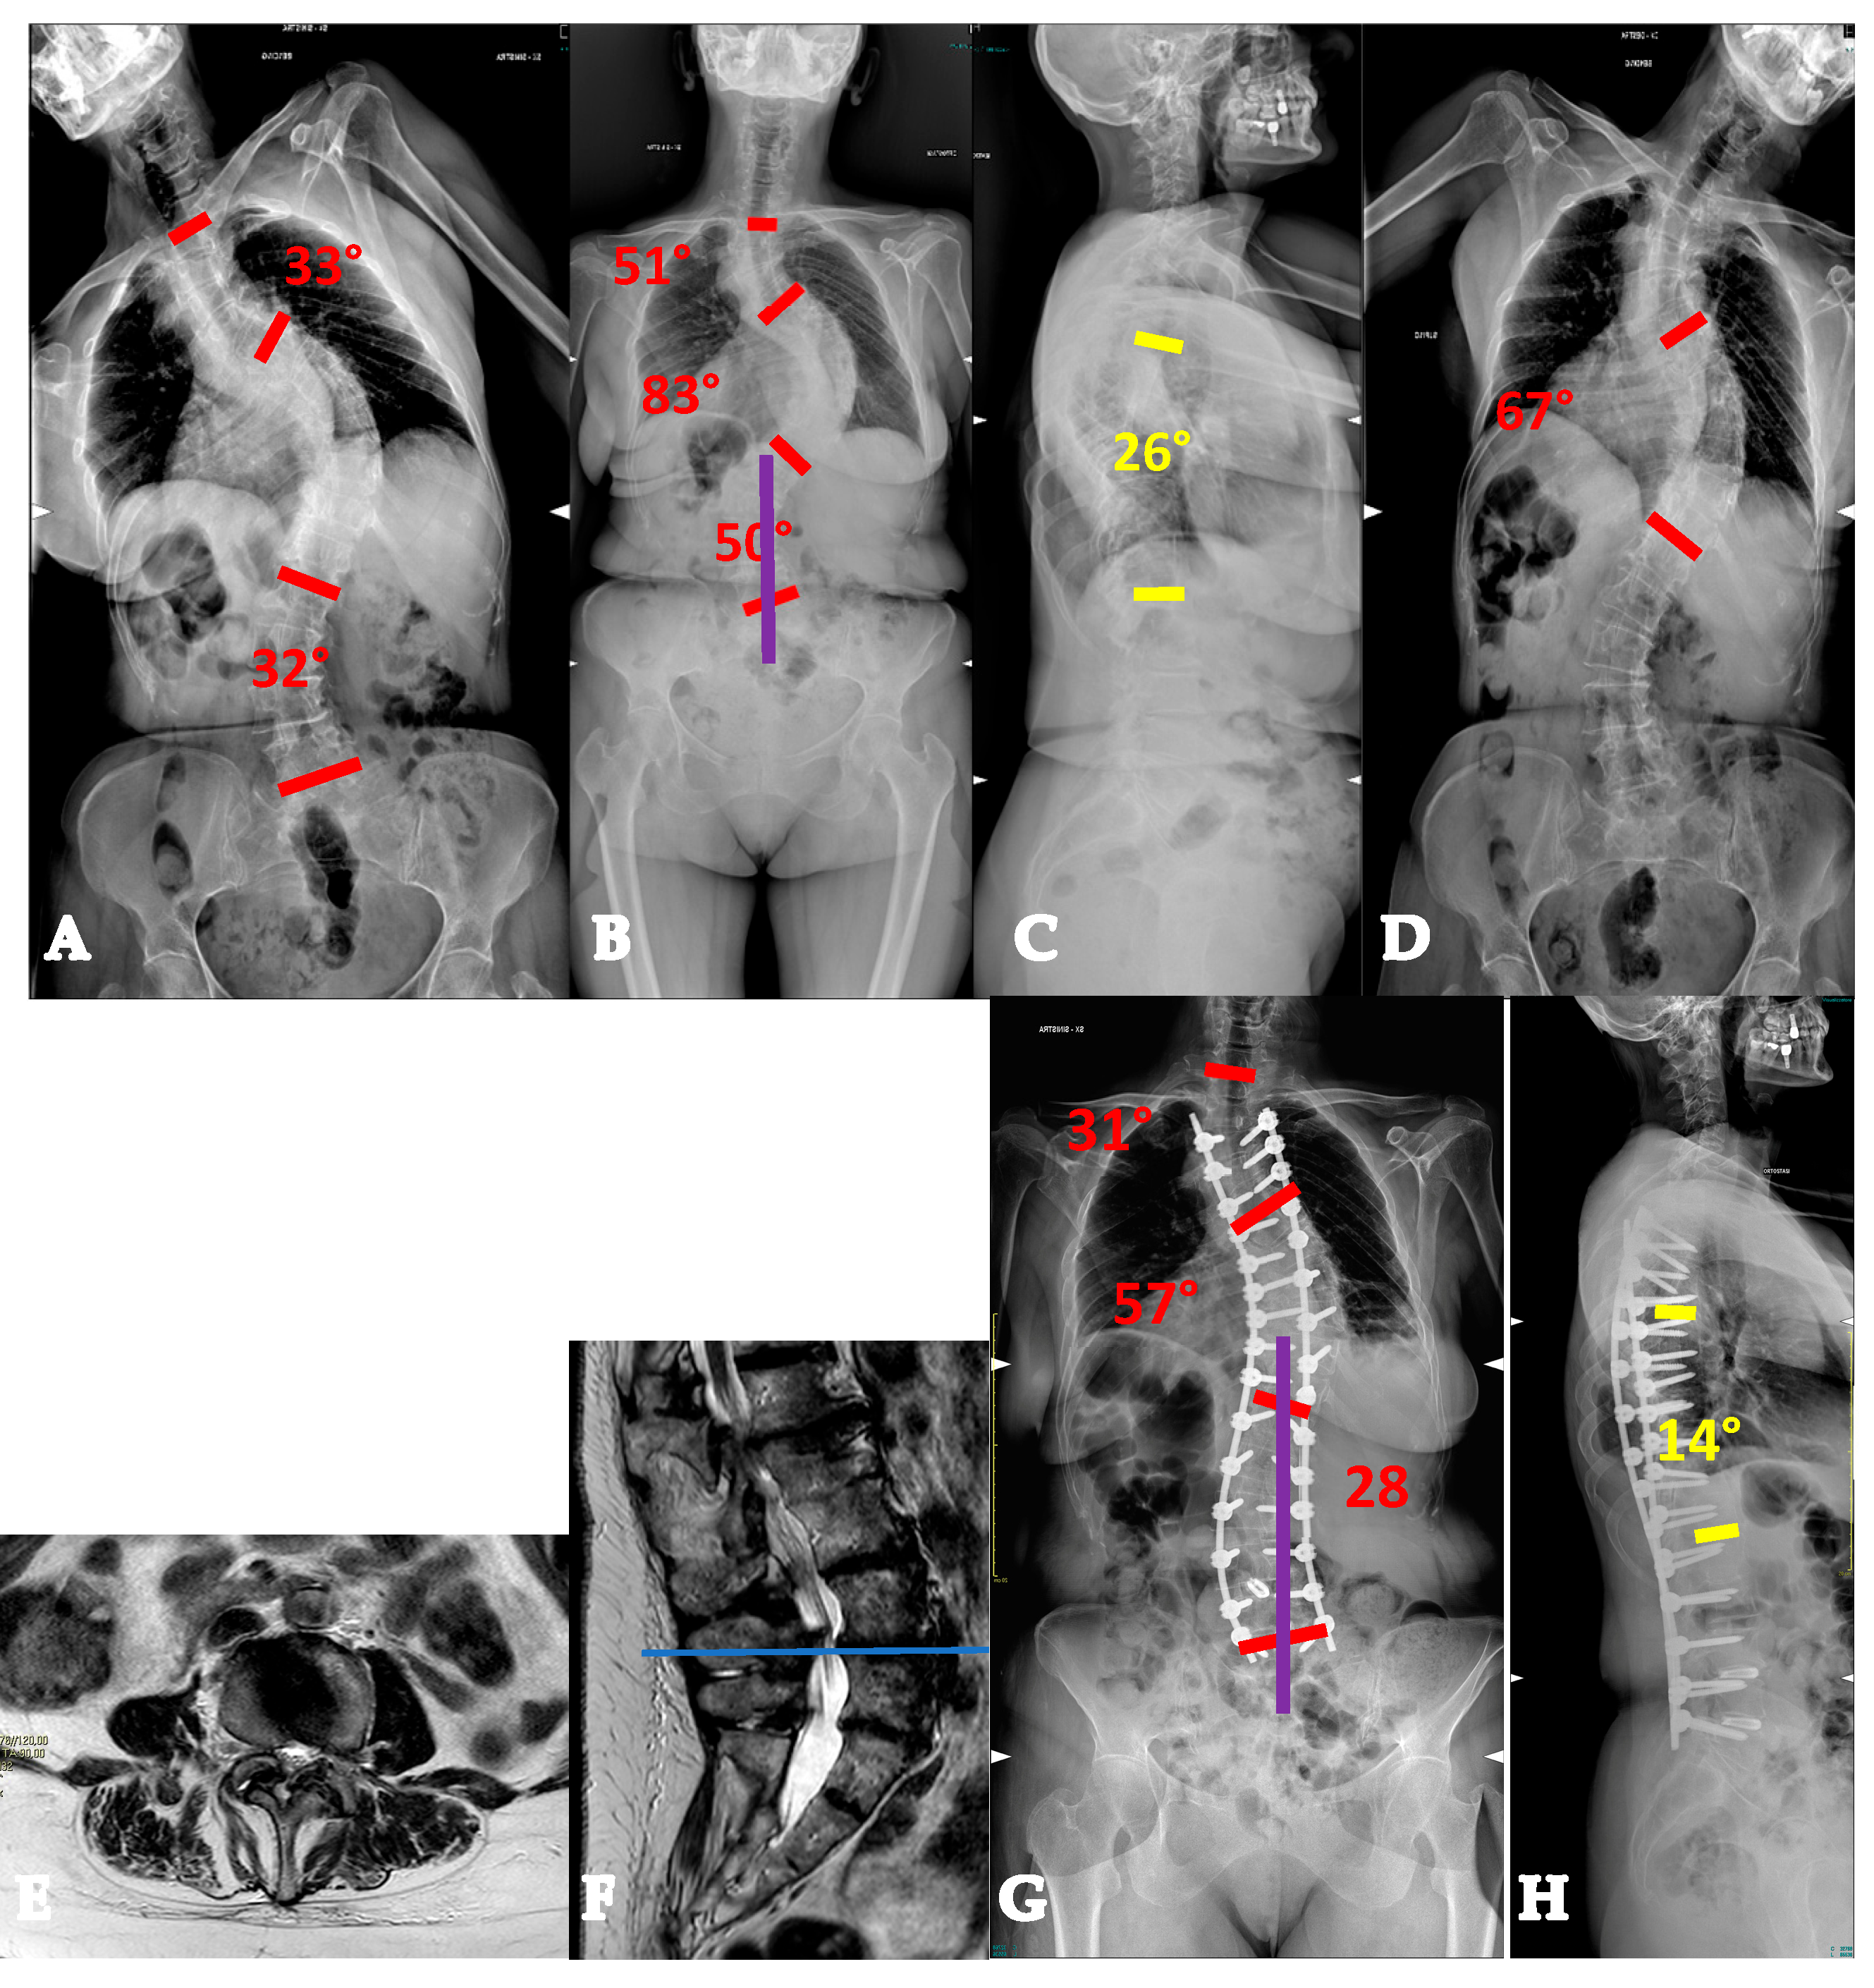

- AdIS 1C: >60 years old. This is infrequent, since patients in this age group more commonly tend to lie in the AdIS 2 group. This group is burdened by an increased stiffness due to an even more frequent anterior column spontaneous fusion, resulting in a less powerful correction both in terms of translation and derotation, with a consequent smaller correction rate and more prominent residual rib hump. However, it must be considered that these patients more commonly present to surgeons because of pain rather than cosmetic concerns. In this view, pain generators should be carefully identified and adequately treated, performing foraminal and/or central decompressions and discectomies where appropriate (Figure 7).